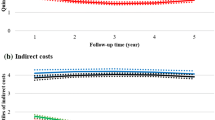

When DMT oral and injectable users were compared, their absenteeism and short-term disability productivity loss and costs were generally similar in the first calendar year (Table 3 and Fig. 2). In the first calendar year of follow-up, the 67 oral users and 201 injectable users with one or more absenteeism claim claimed a mean (SD) of 274.2 (215.0) and 333.9 (263.3) absenteeism hours, respectively, of which 120.0 (211.6) and 169.1 (255.5) hours were non-recreational, respectively. The corresponding absenteeism costs were US$7258 (US$5691) and US$8839 (US$6969) in the first year over a period of 176.0 (112.4) and 188.4 (108.1) days, respectively. The 150 oral users and 433 injectable users with one or more short-term disability claims took, on average, 69.9 (54.4) and 68.8 (50.4) short-term disability hours in the first calendar year over a period of 179.4 (102.5) and 186.1 (106.1) days, respectively. The corresponding mean (SD) short-term disability costs were US$10,368 (US$8066) and US$10,204 (US$8116), respectively.

While the number of patients with one or more long-term disability claims was low (oral: n = 21; injectable: n = 47), the mean (SD) number of long-term disability days taken by oral users was less than half the number of days taken by injection users (31.7 [49.9] vs 76.3 [86.0]; p = 0.031) in the first year of follow-up (Table 3). The estimated mean long-term disability costs among patients with one or more claims were US$6609 (p = 0.031) lower for oral users than injection users (Fig. 2).